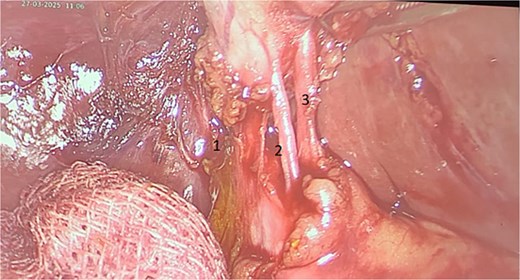

Surgery was performed after stabilization for elective cholecystectomy (Fig. 1). Intraoperatively, a double cystic duct was identified and managed successfully (Fig. 3). Pathology confirmed chronic cholecystitis with no malignancy.

Intraoperative image showing three elements: Cystic artery (3) and two cystic ducts (1, 2).